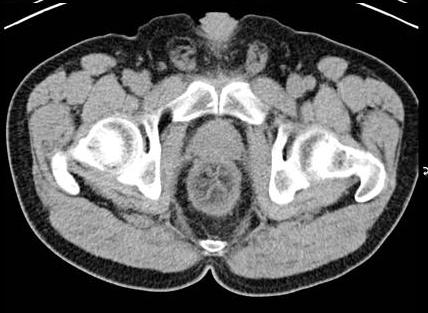

. Image TDM du maladie de

Crohn dans phase aigue est image

de epaissisement parietale avec oedeme sous muqueuse

discontinunite et signe de peigne " comb sign ". En phase

chronique cicatricielle ,aspect radiologique est image

epaissisement homogene de la paroi avec infiltration graisseuse parietale ou mesenterique

en forme de image de cible " fat halo sign". Stenose ,fistule et

abces sont des images de sa complication .

Stenose epaisissement colique

gauche et sigmoidienne avec halo graisseux d'une

maladie de Crohn . Image de hypervascularisation et

infiltration de la graisse sous-muqueuse , aspect en

peigne " Comb sign ". Image TDM en coupe coronale |

|

Image de

hypervascularisation " Comb sign " et epaissisement

de la paroi du ileon se voyait si nette sur les

coupe TDM axiale |